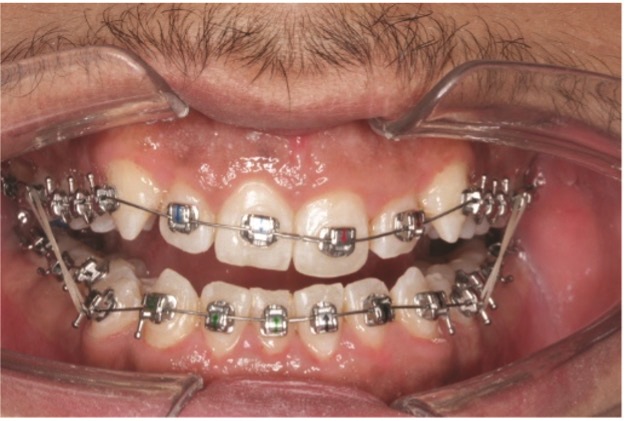

Passive self-ligating braces with 0.0215-by-0.0275-inch slot dimension (Genius, MEM) were directly bonded from 7–7, and 14 thermally activated nickel titanium wires (Thermal Ultra, MEM) were inserted, delivering 25 g for 1.5 mm of wire deflection. Stops were placed on upper and lower wires at midline. Immediate Class III elastics (2.5-ounce, 3/16-inch, worn full time) ran from the upper first molar to lower first bicuspids bilaterally. Disarticulation required light-cure band cement (Bandlock, Reliance Orthodontics) on the palatal cusp of upper second molars (Figs. 3a–3c).

dentoskeletal-malocclusion

Fig. 3a

Fig. 3b

Fig. 3c